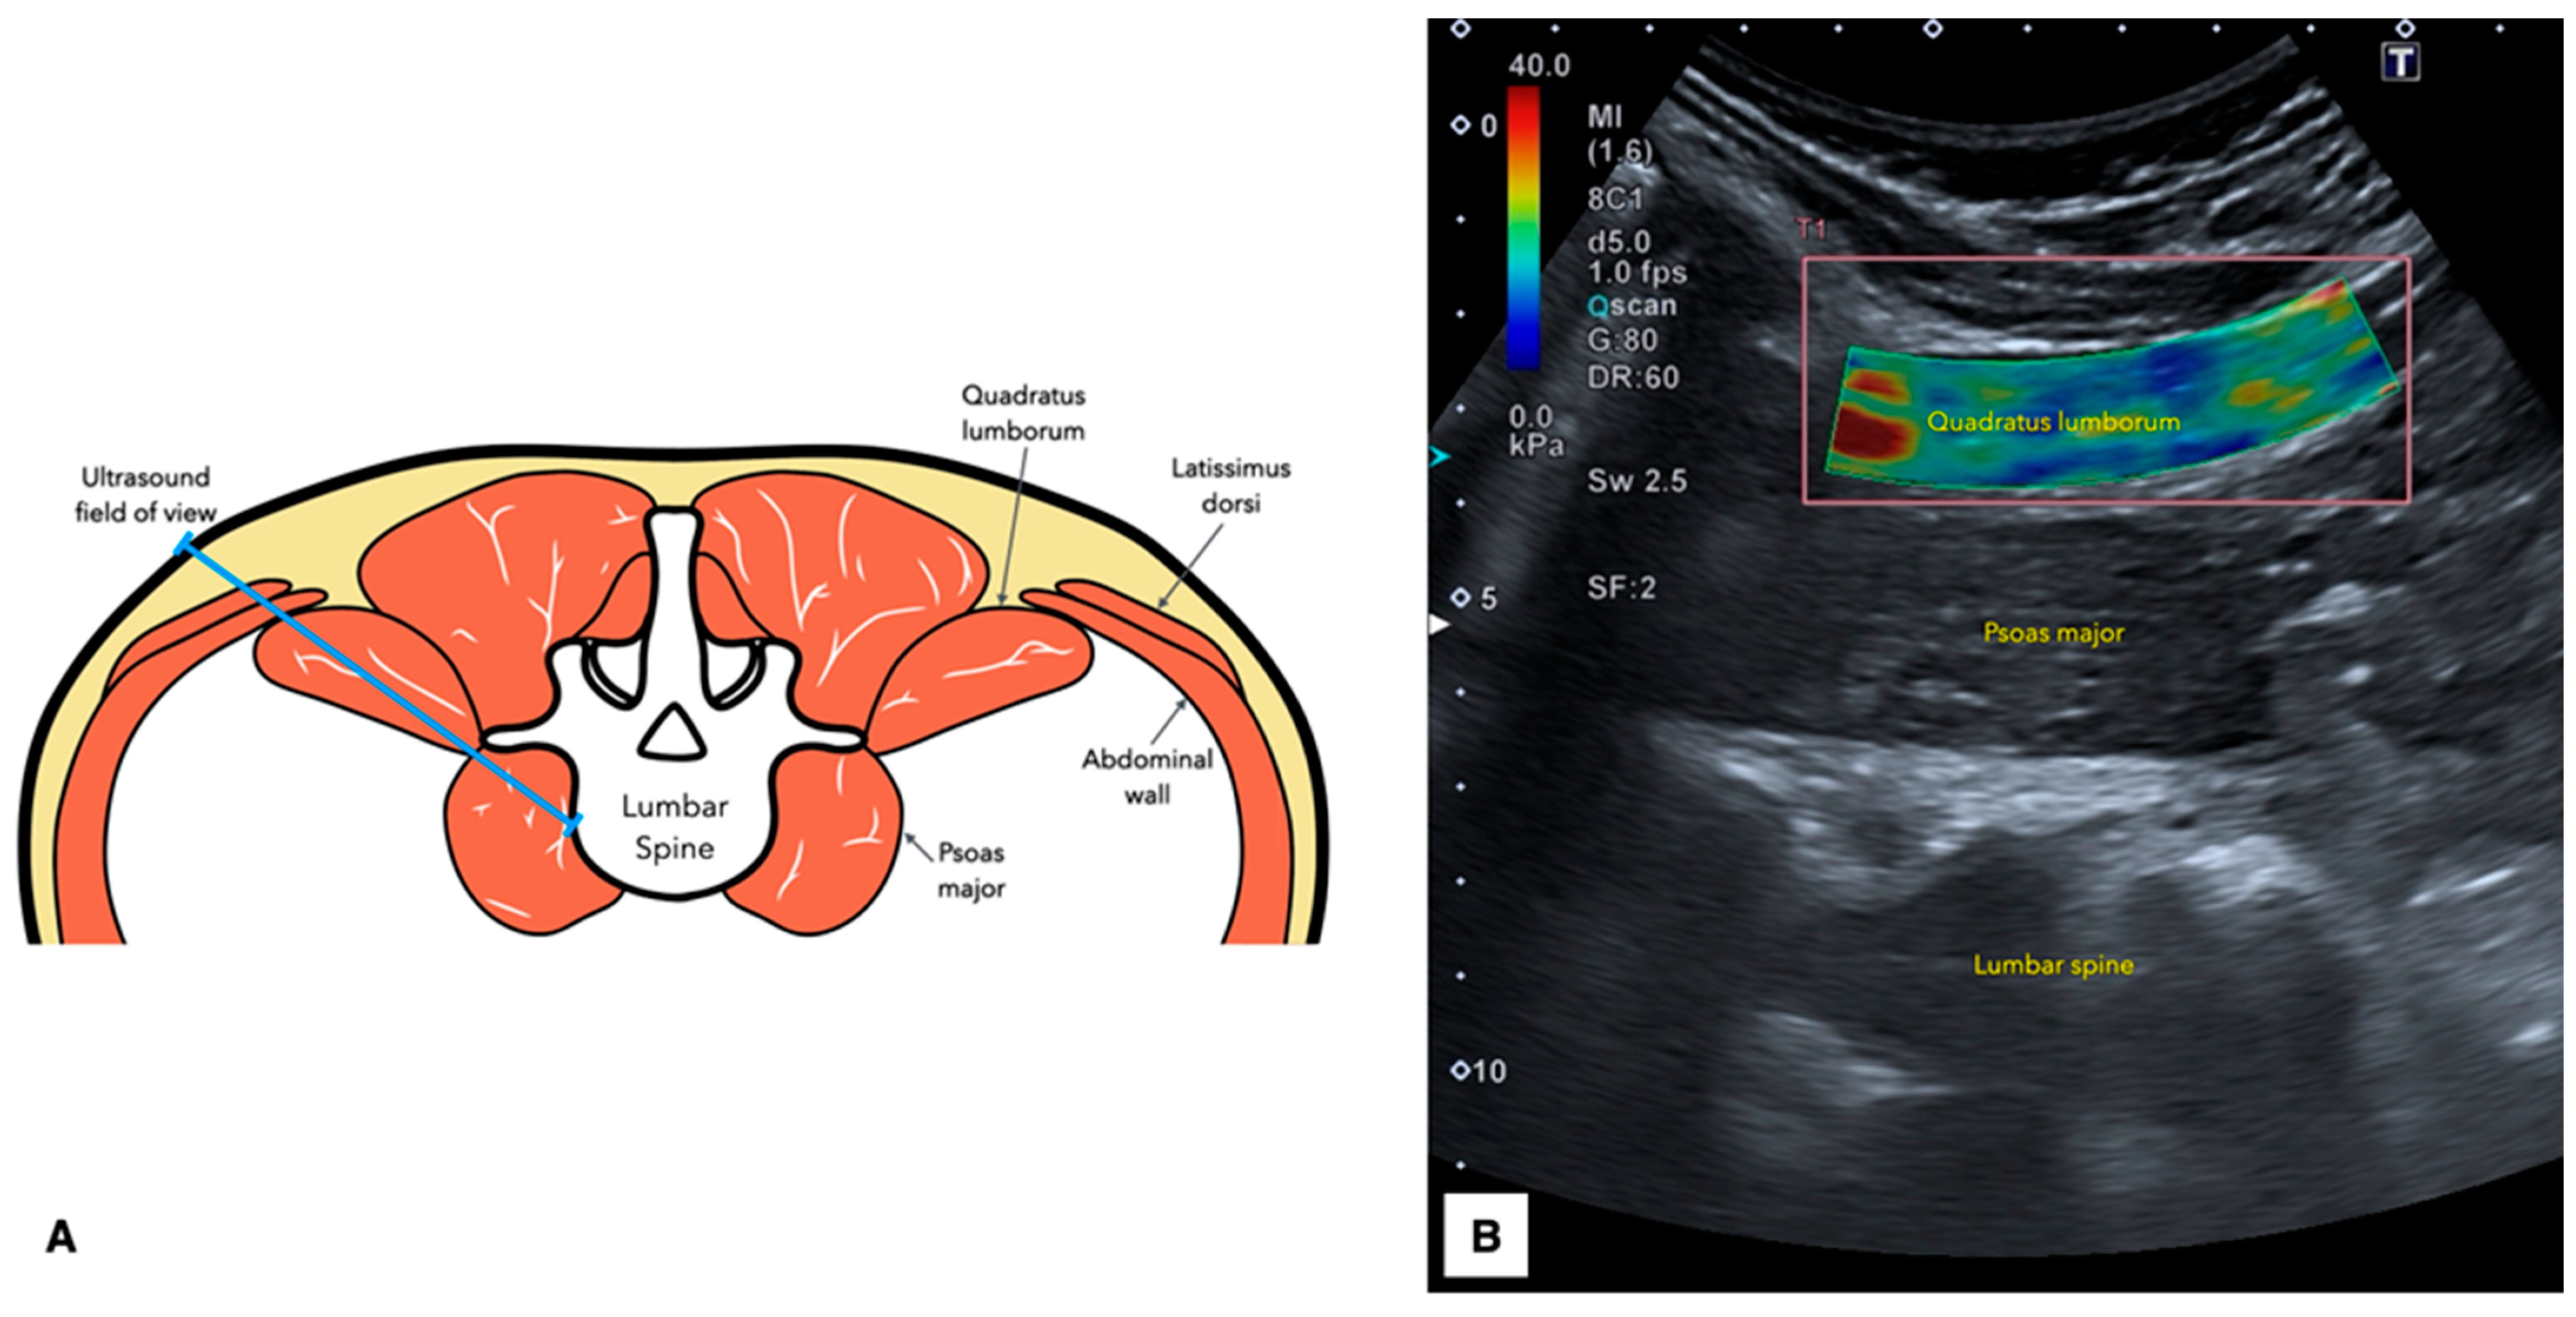

2.5. Ultrasound Imaging Acquisition Protocol